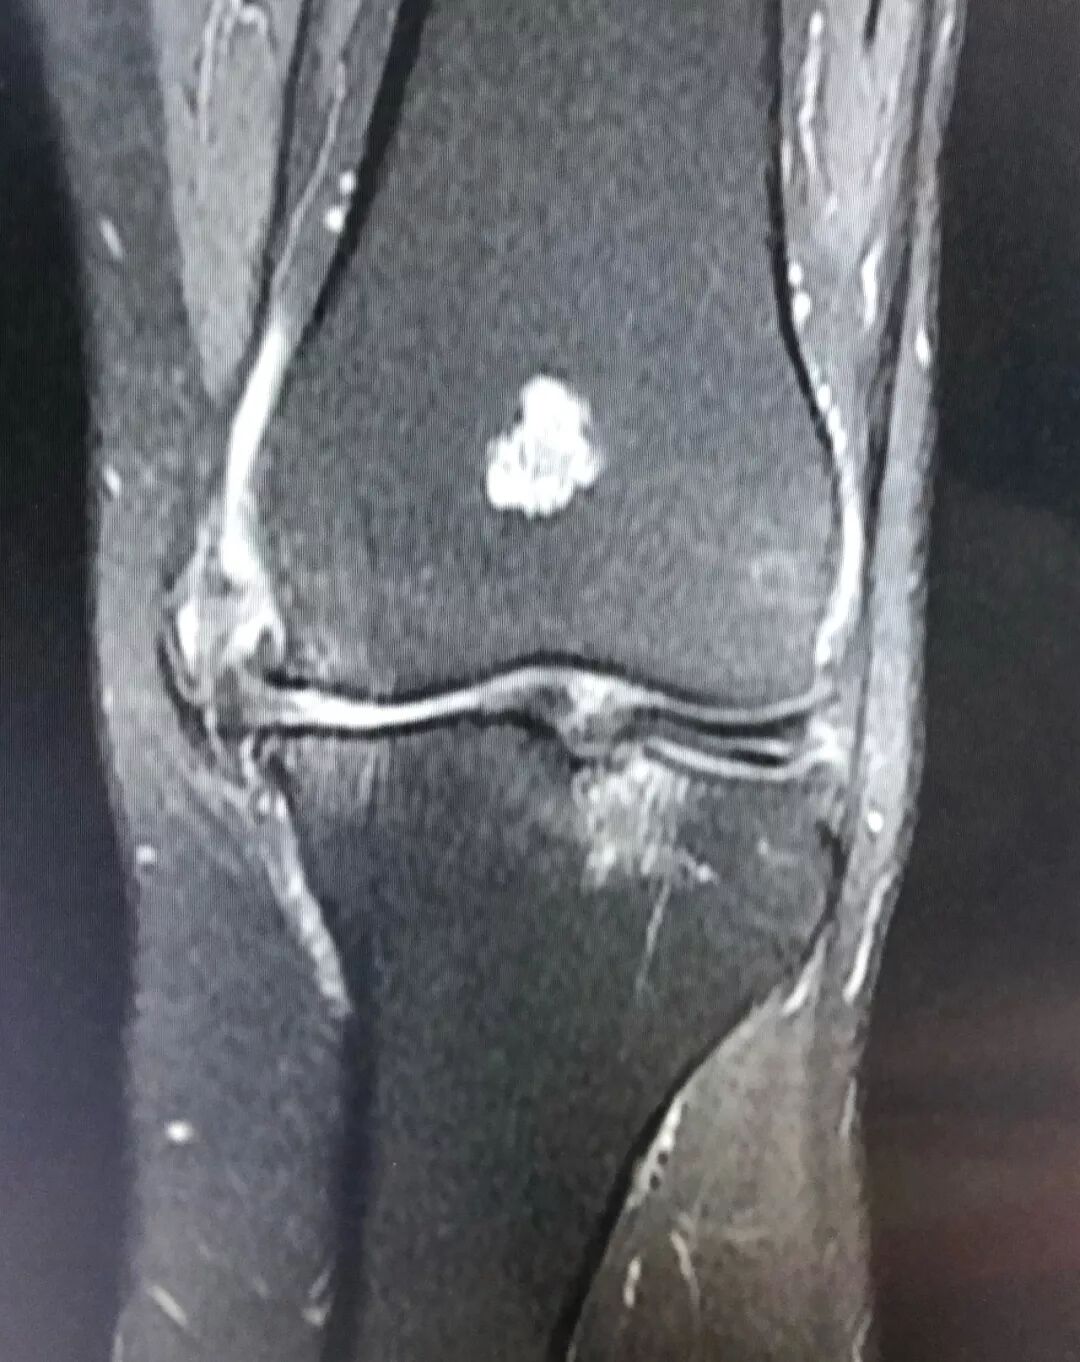

全膝关节置换术让膝关节疾病患者重获新生

MRI